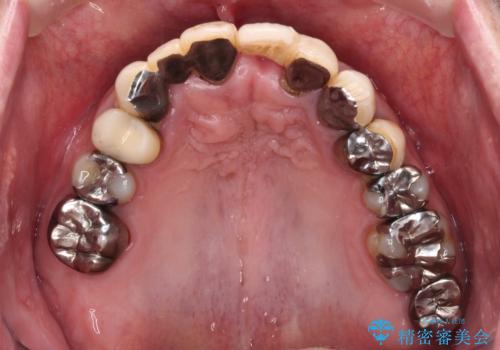

転倒で折れてしまった前歯 インプラントによるオールセラミックブリッジ治療

- 転倒により前歯3本が折れてしまったとのことで、インプラントによる治療を希望して来院された患者様です。

既に近医で真ん中の歯1本は抜歯されており、その隣の2本も破折していると言われたとのことでした。

診断をした結果、前医の診断の通り、2本とも破折しており、既に抜去している歯を含めて3本の抜歯が必要な状態でした。

抜歯する歯の両隣も治療が必要と思える歯であったため、広範囲なオールセラミックブリッジによる治療も提案しましたが、患者様本人の希望もあってインプラント2本による欠損部のみのブリッジ治療を行うこととしました。